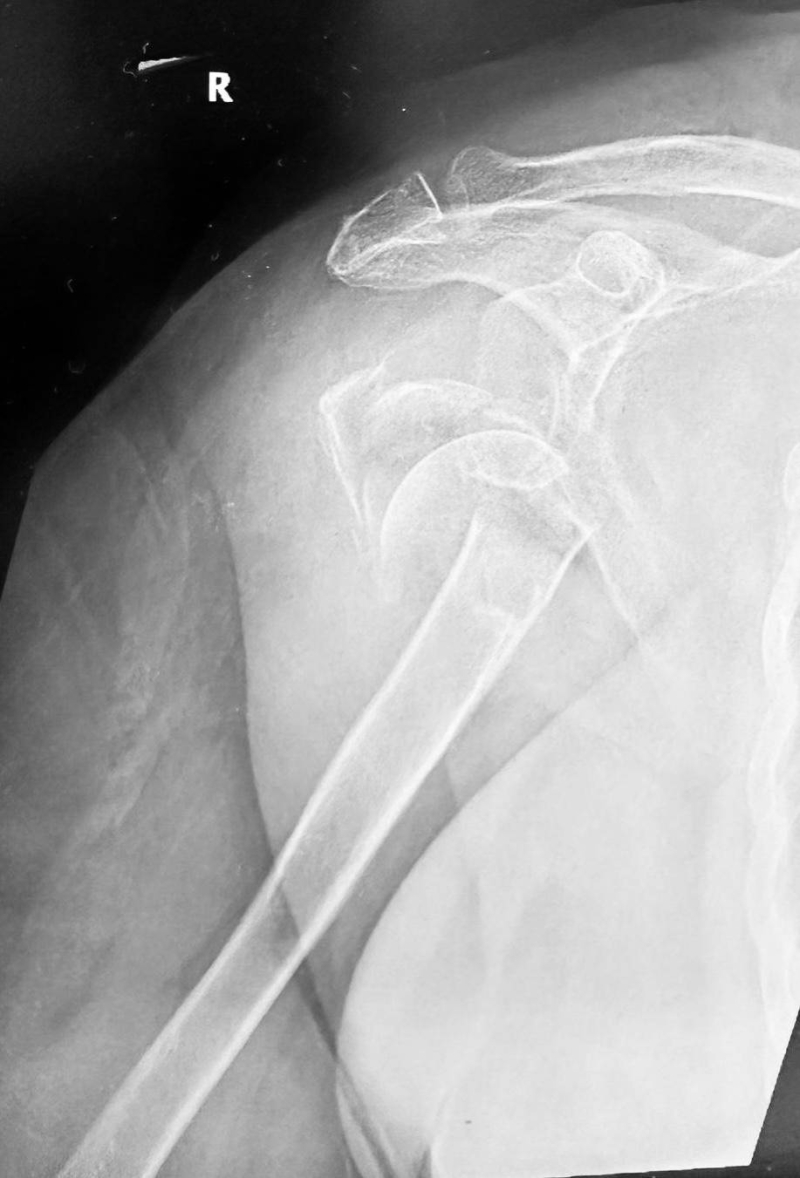

أعلن رئيس قسم العظام في مستشفى الفروانية الدكتور محمد مفيد عن إجراء أول عملية استبدال مفصل كتف كامل من النوع العكسي في المستشفى، تحت إشراف الدكتور بدر البشاره اختصاصي جراحة العظام وجراحة الكتف، وذلك لمريضة متقدمة في العمر بسبب كسر معقد ومتقدم في مفصل الكتف أفقدها القدرة على حركة المفصل.

وأوضح الدكتور مفيد في تصريح لـ «الراي» أن هذه العملية تعتبر من الجراحات المتقدمة في مجال جراحة مفصل الكتف، ونتائجها ممتازة خاصةً عند إجرائها في حالات الكسور المعقدة لكبار السن أو في حالات الخشونة المصاحبة لقطوع أوتار الكتف المزمنة.